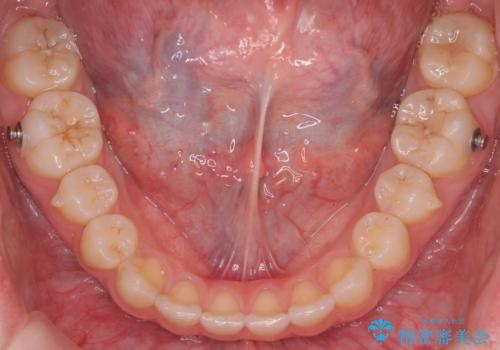

咬んでも向こう側が見える、前歯が閉じない症状でした。また、上の前歯が少し前に出ている状態でした。

上の前歯をわずかに削る処置を行い、後ろに下げながら下の歯となるべく咬むように矯正治療を行いました。